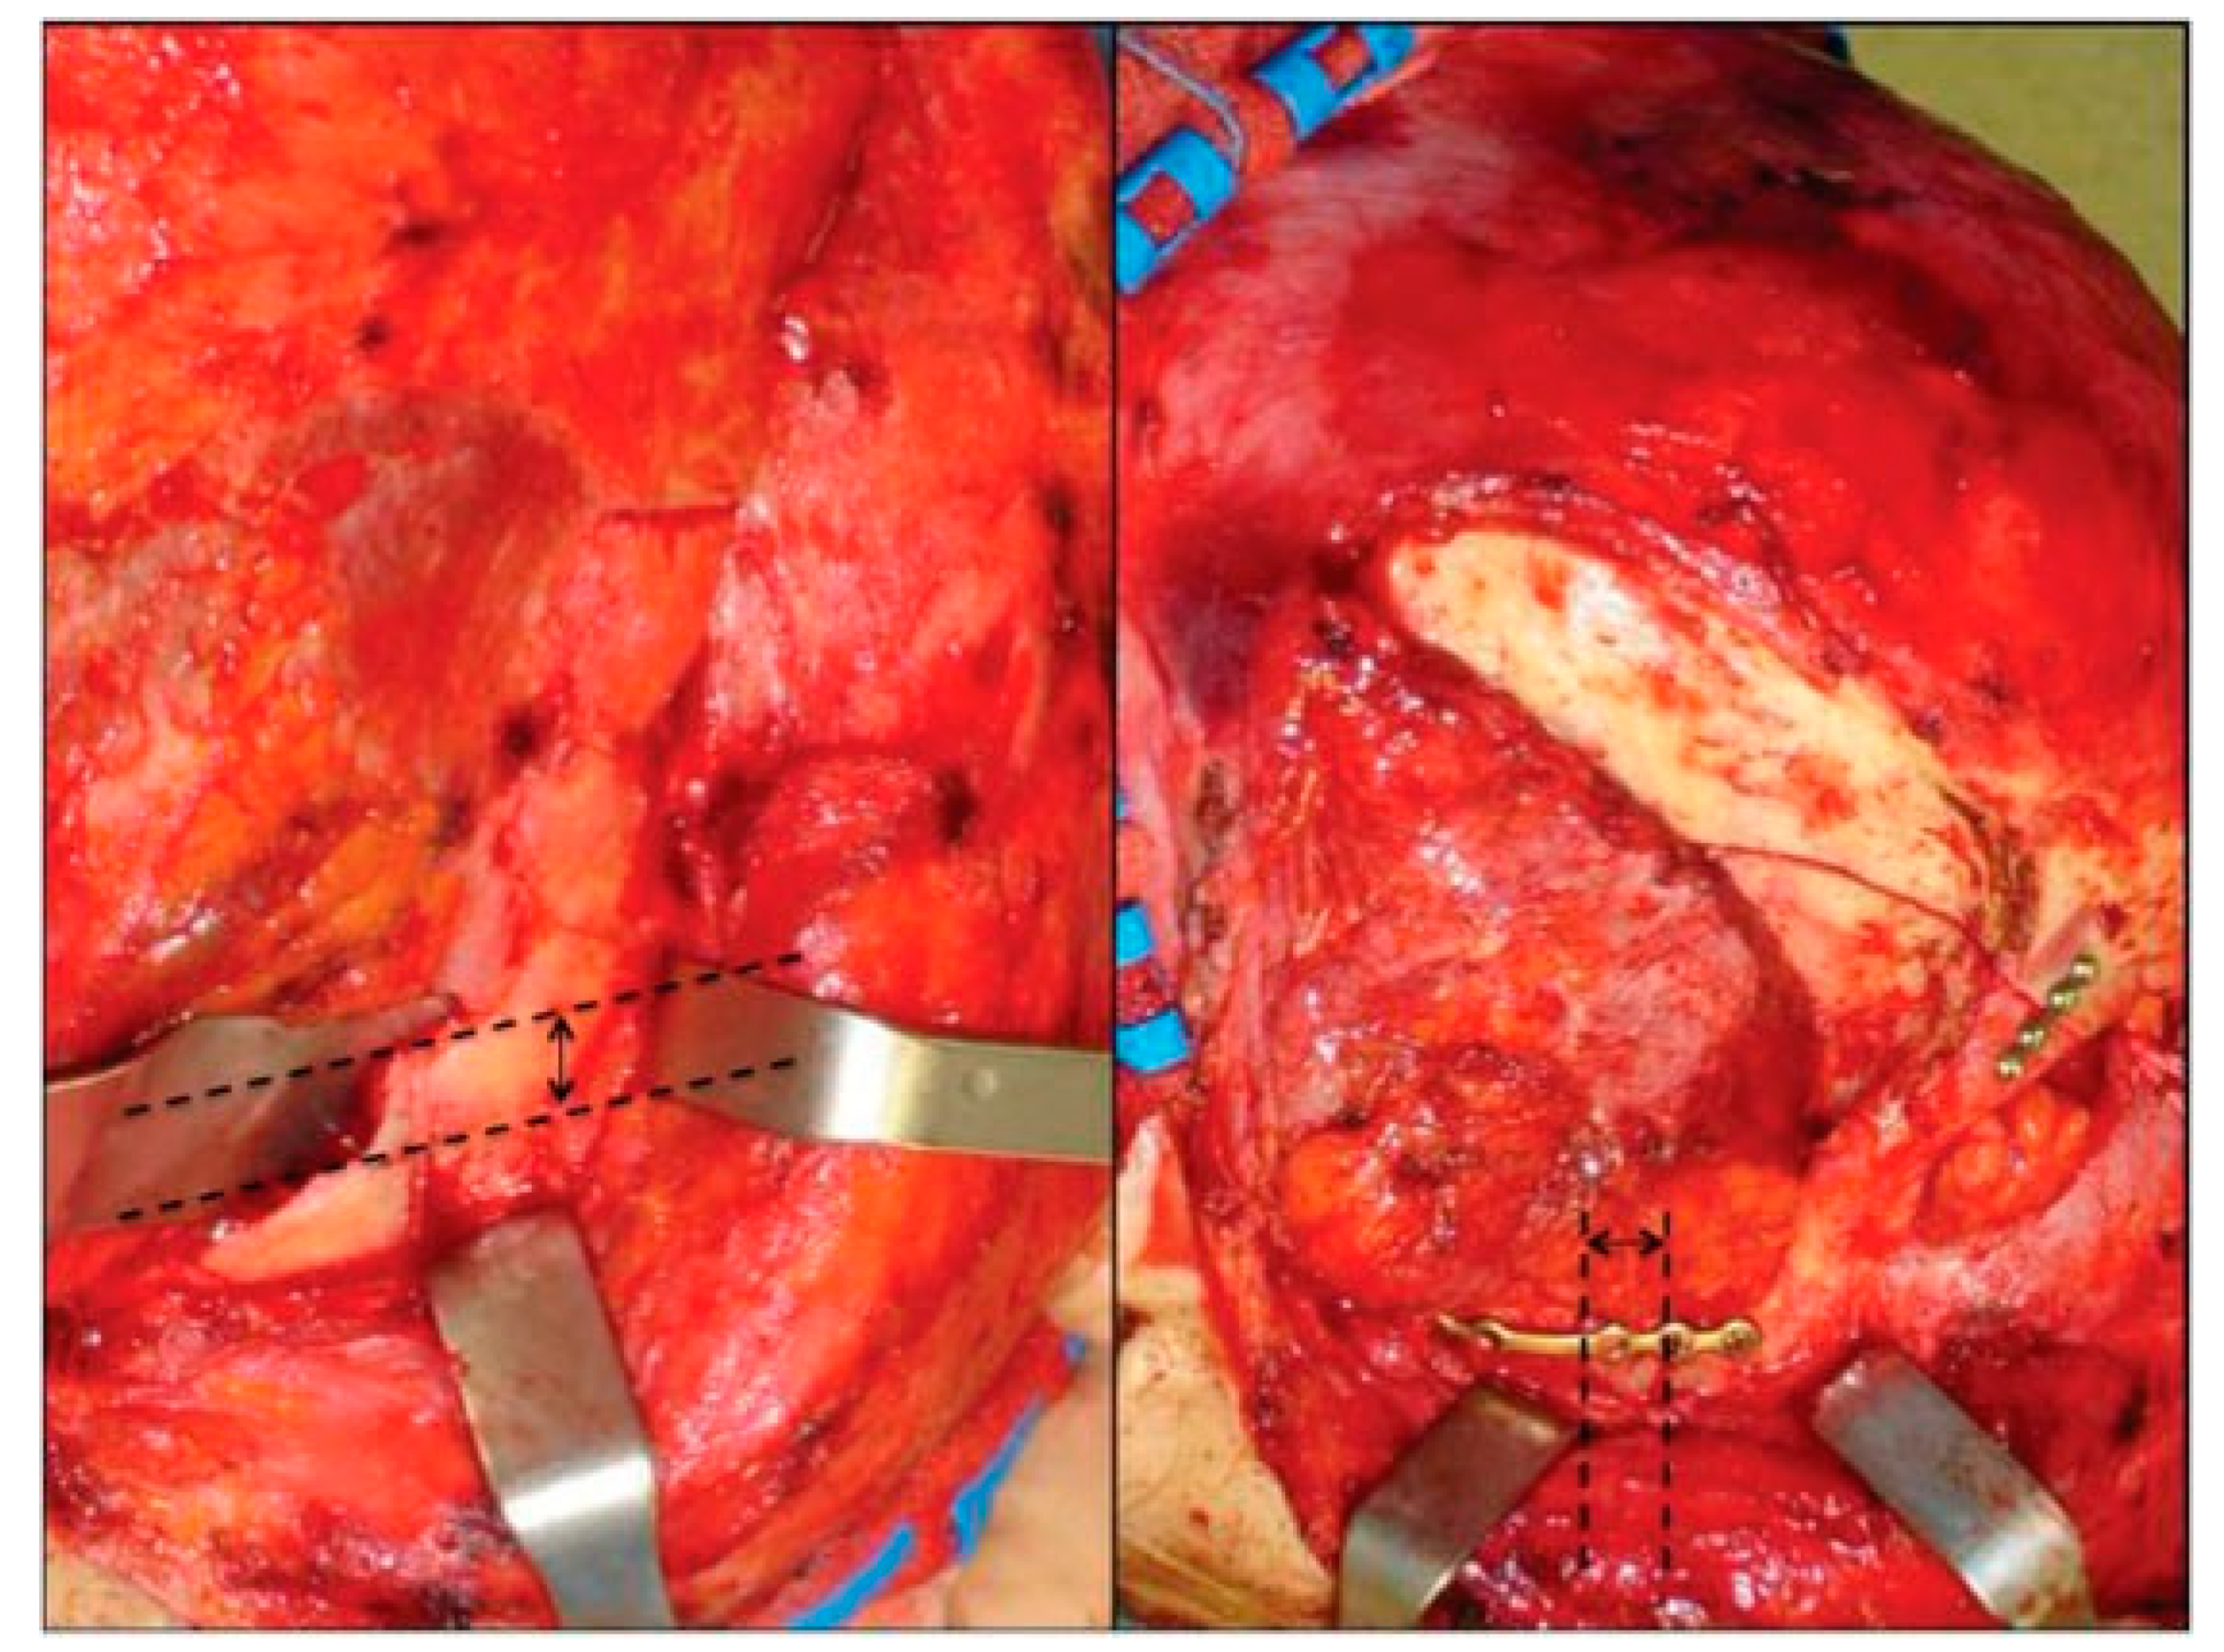

After 72 hours without any clinical improvement despite the steroid treatment, the patient underwent surgery. A bicoronal flap was harvested and only smooth exploration of the orbital roof and of the lateral orbital wall up to the SOF was performed, to exclude both undetected bone fragments displaced and subtle subperiosteal hematomas. The right temporalis muscle was completely dissected to achieve the complete exposure of the infratemporal fossa to master the frontotemporal skull portion of the fracture and an open standard Gillies elevation with Volkmann Bone Hook (Sklar Surgical Instruments, West Chester, PA) was performed, followed by internal rigid fixation at the right zygomatic arch and at the frontal–temporal buttresses (Figure 3).

Figure 3. Left: Intraoperative view before reduction; right: Intraoperative view after reduction and rigid internal fixation. Black arrow shows displacement entity.